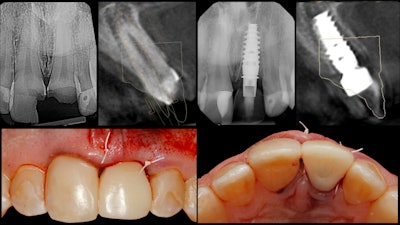

This patient presented with severe coronal caries for teeth #8 and #9. Anticipating both teeth to be nonrestorable, a treatment plan for two implants was developed (figure 1). Before treatment, the patient's intraoral condition was imaged using the Cerec Omnicam (Dentsply Sirona). A CBCT image was obtained using the Orthophos XG 3D.

We merged the patient's two datasets (teeth and soft tissue and also osseous information) using implant treatment planning software. From this we developed a prosthetically driven virtual surgical plan. At that point, we also designed a surgical guide that was 3D-printed in advance of the implant placement surgery (figure 2).

Then we used a prefabricated surgical guide to direct the osteotomy drill sequence, immediately placing the NobelActive implant fixture (Nobel Biocare) in a fully guided fashion (figure 3).

With the implant torqued into place at greater than 50 Ncm, a digital ScanPost (Denstply Sirona) was then placed and imaged to facilitate the design of a Telio CAD (Ivoclar Vivadent) screw-retained immediate provisional using the Cerec Chairside CAD/CAM software (figure 4).

When the procedure was completed, verification radiographs were compared with the preoperative plan.